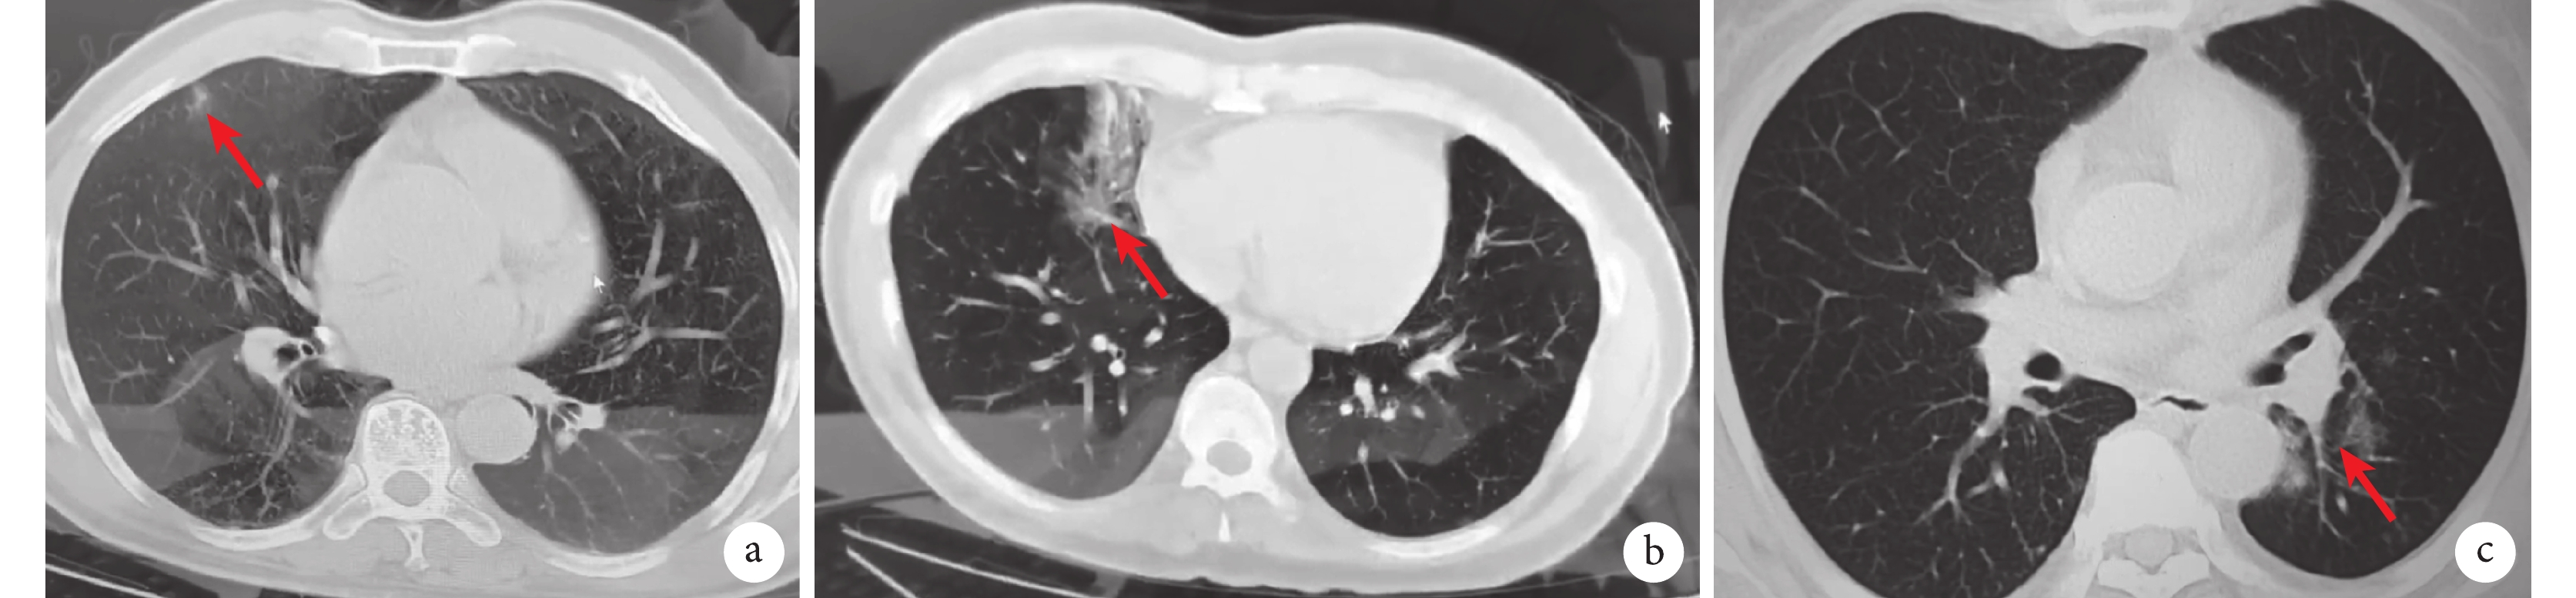

方艙醫院患者平均住院時間(7.39±0.53)d,其中60歲以下患者住院時間(7.01±2.12)d,60歲以上患者住院時間為(8.21±0.82)d,老年患者住院時間長于非老年患者(P≤0.01,表3),且未接種疫苗的60歲以上老年患者住院時間顯著長于方艙患者和接種疫苗的老年患者平均住院時間[ (8.94±1.71)d vs.(7.83±1.44)d,P≤0.01,表4]。住院時間長于10 d的患者16 211例,占患者總數的9.3%。方艙醫院患者除給予中藥湯劑治療外,其它藥物主要為感冒、上呼吸道感染等其它對癥治療,主要用藥物見表5。針對呼吸道癥狀嚴重、血氧飽和度低于正常或長時間未轉陰的患者,積極進行胸部CT檢查。此次方艙醫院患者行CT檢查結果中,大部分患者無肺部受累表現,僅極少部分患者存在肺部炎癥感染表現(圖3)。對于呼吸道癥狀進行性加重、基礎疾病重缺乏治療手段、精神類疾病以及活動不便的老年患者,視病情變化和核酸轉陰情況進行轉院治療,累計轉定點醫院治療2 085例患者。

紅色箭頭示肺部感染受累表現;a:男,63歲,胸痛、氣促;b:男,39歲,咳嗽咳痰進行性加重,咳嗽時伴呼吸困難;c:女,65歲,咳嗽,頭痛